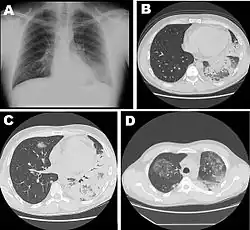

Différents stades de la maladie. Radiographie thoracique (A) et une tomodensitométrie à haute résolution (B) à la date d'hospitalisation. Tomodensitométrie du thorax une semaine après l'hospitalisation (C, D), d'un homme de 42 ans atteint d'une pneumonie grave causée par la Legionella pneumophila du sérogroupe 11a.

La radiographie du thorax peut montrer un infiltrat pulmonaire ainsi qu'un épanchement pleural. Les images peuvent persister un certain temps après la fin du traitement[26].